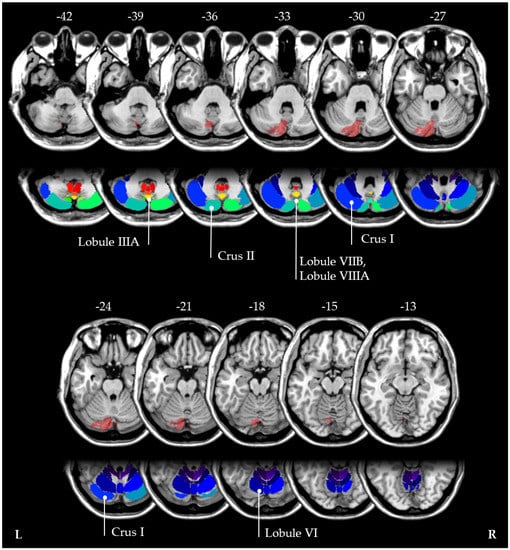

To classify the neuroanatomical localization of the patient’s lesion, we used images from a second control MRI which was performed ten weeks after stroke. First, the patient’s individual cerebral lesion was manually delineated on individual structural MRI images using the open-source MRIcron software (https://www.nitrc.org/projects/mricron/, accessed on 17 February 2022). The borders of the lesion were manually delineated on every transverse slice of the individual MRI images. Then, images were normalized into MNI space with the Clinical Toolbox for SPM ([31]; https://www.nitrc.org/projects/clinicaltbx/, accessed on 17 February 2022), using enantio-morphic normalization [32], and running in SPM12 (http://www.fil.ion.ucl.ac.uk/spm, accessed on 17 February 2022). Furthermore, the “cerebellar atlas” that comes with FSL was used [33]. This revealed that the stroke affected crus I and II, as well as lobules IIIA, VI, VIIB and VIIIA (see Figure 3). Interestingly, the latter two lobules have been previously discussed as hubs for ipsilateral visuospatial cognition [34].

Figure 3.

The MNI coordinates of the normalized cerebellar lesion (10 weeks post-stroke) are shown. Neuroanatomical localization of the patient’s lesion using FSL [33] revealed that the stroke affected crus I and II, as well as lobules IIIA, VI, VIIB and VIIIA.

Third, the heterogenous results regarding ipsi- and contralateral neglect might have anatomical reasons. For instance, in most of the above-mentioned previous studies, it was not clearly stated whether the strokes were purely isolated to the cerebellum, or whether additional brainstem structures were also affected. Theoretically, it is possible that additional afferent or efferent cerebellar fibres might also be damaged [7], which could explain the reported discrepancies between ipsi- and contralateral neglect occurrence. In this context, it is interesting to note that in our patient, the stroke affected the left lobules VIIB and VIIIA. These regions have recently been discussed as hubs that code key aspects of ipsilateral visuospatial representations [34].

In summary, the present findings suggest that not only executive, language, and affective deficits may occur within the framework of the Schmahmann Syndrome [6], but also, particularly if lobules VIIB and VIIIA [34] are affected, visual neglect. Furthermore, these findings underline the view that the cerebellum has a modulatory role on cortical function [4]. Neuroanatomical and physiological results evidenced cortico–cerebellar circuits connecting the cerebellum to the contralateral association cortex [1,7]. In particular, in case of a PICA stroke, the ventral posterior cerebellum might become disconnected from contralateral parietal and associative areas [45]. It seems therefore plausible that a PICA stroke might result in hypoactivation and diaschisis within the corresponding contralateral telencephalic hemispheric cortical networks [3], leading to neglect after a left-hemispheric PICA stroke and to aphasia after a right-hemispheric PICA stroke.